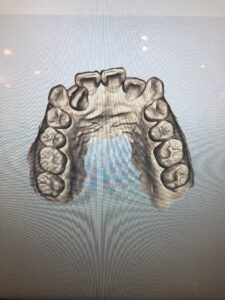

「iTero」で撮影した3Dデータは、このように色々な角度から動かして見ることができるので、自分の歯はこんな形をしているのか!など新発見があるかもしれません。